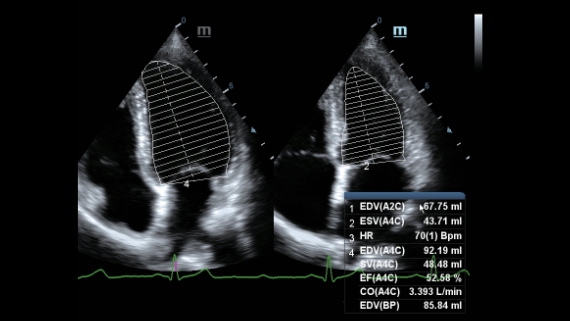

?ok y?nlĂŒ bir partner olarak, X-Insight'l? DC-60 Exp, her y?nĂŒyle gĂŒnlĂŒk klinik uygulamay? kolayl?kla ve belirsizlik olmadan y?netmenize yard?mc? olacak kapsaml? bir ??zĂŒm sunar.

MĂŒ?teri gereksinimlerine y?nelik g?rĂŒ?ler temelinde, X-Insight'l? DC-60 Exp, eXpress Clarity, eXceptional Intelligence ve eXceeding Experience ile gĂŒ?lendirilerek, hassas g?rĂŒntĂŒlemeyle yĂŒksek verimlilik sa?layacak ?ekilde tasarlanm??t?r.

eXceeding Experience

YĂŒksek verimli deneyim